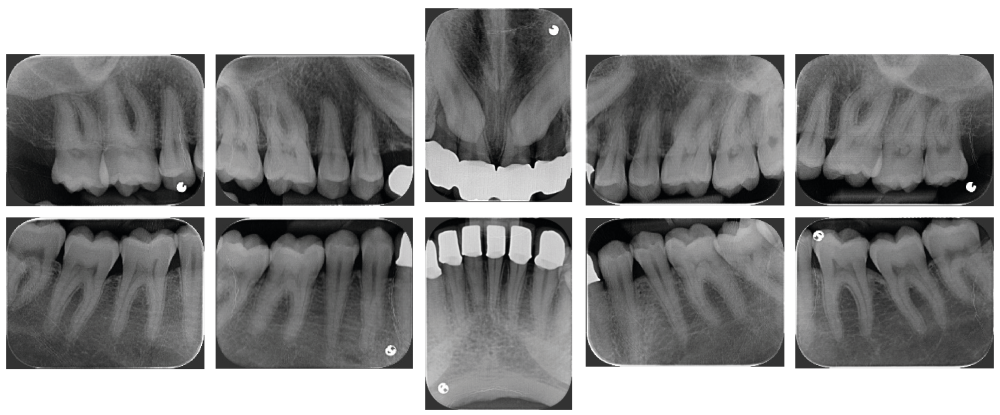

À l’examen endobuccal de première consultation (fig. 1), nous notons la présence d’un bridge maxillaire céramo-céramique sur infrastructure en zircone avec 12, 11, 21 et 22 couronnes moyens d’ancrage et 13 et 23 intermédiaires de bridge en extension. Les incisives et canines mandibulaires ont également été couronnées individuellement. Le patient nous informe que ces soins ont été réalisés pour répondre à sa demande esthétique. L’examen radiologique (fig. 2) révèle la présence de deux canines maxillaires incluses et nous montre qu’aucune dent n’a subi de traitement endodontique.